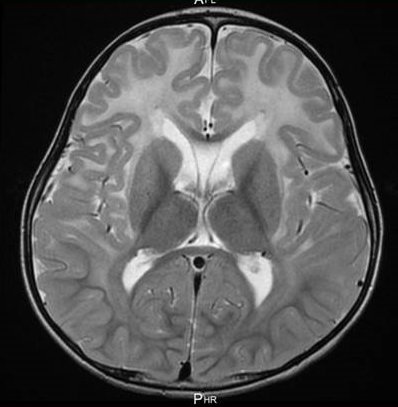

現在では脳の画像を描出できるMRI検査を用いると、前頭葉(ぜんとうよう)と呼ばれる脳の前方に「白質病変(はくしつびょうへん)」として、不自然に写ります。しかし、MRIが存在しない時代は、患者さんが生きている間にアレキサンダー病の診断をすることは非常に困難だったのです。

いずれも多くの症例が精神運動発達遅滞を伴います。MRI検査では、症例により程度の差はありますが、前頭部の白質病変と延髄の萎縮といった大脳優位型と延髄・脊髄優位型の両者の特徴を認めます。